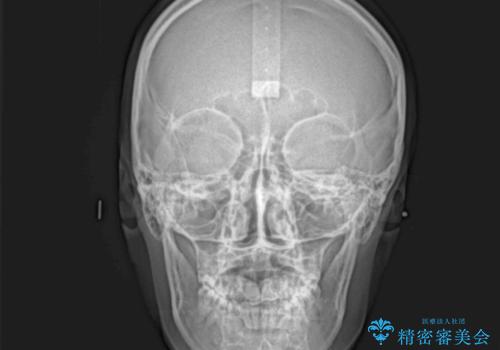

急速拡大装置による上顎骨の側方拡大が思った以上にうまくいき、非抜歯での矯正が可能となりました。

内側に倒れていた下顎の臼歯は起き上がり、清掃性も大幅に改善されました。